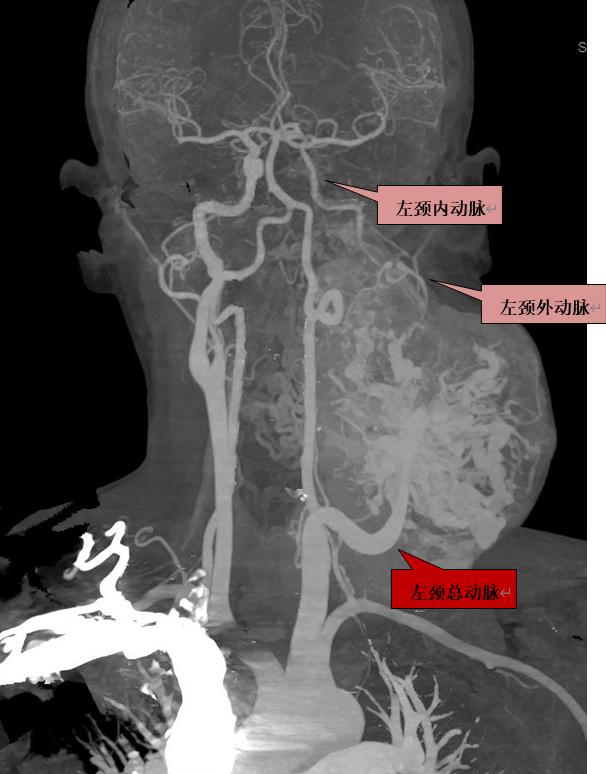

扫描过程中医生抓住动静脉最佳显示时间,分别行动脉和静脉血管成像(CTA,CTV)。

当分别进行完动脉和静脉CT血管重建后,发现患者颈部肿块由颈总动脉供血,强化非常明显,肿块的上方发出两根纤细的颈内动脉和颈外动脉。